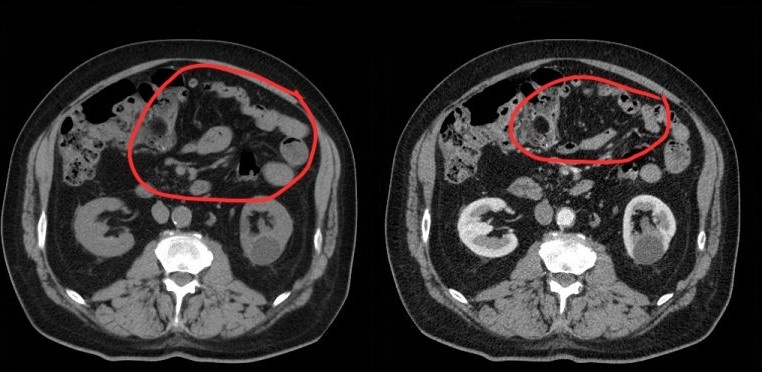

Аксиальные срезы в нативную и артериальную фазы исследования. Плотность брыжейки не отличается от плотности жира иной локализации. Киста нижней трети левой почки, Bosniak I

Брыжейка в норме легко визуализируются за счёт жировой ткани. В ней хорошо различимы сосуды, могут встречаться единичные неувеличенные лимфатические узлы.

Для сравнения: вид брыжейки при панникулите. На самом деле, мутная.